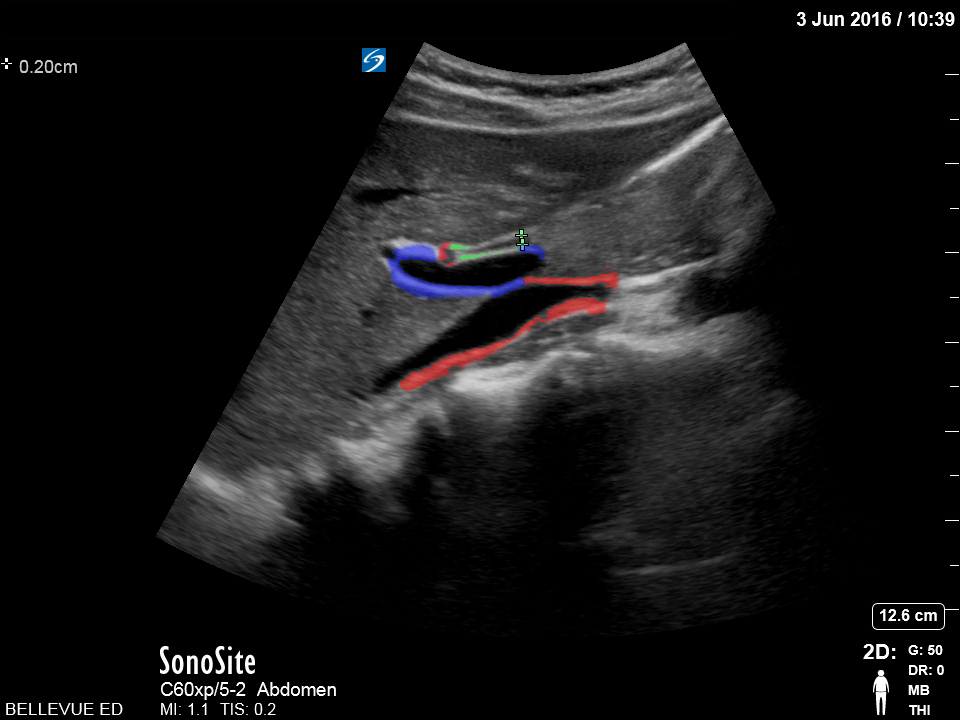

Biliary - Olive Sandwich Sign - Colorized

Olive Sandwich Sign Red (small): “Olive” or hepatic artery, Green: Common bile duct, Blue: Portal vein, Red (large): IVC Images: Dr. Lindsay Davis, Dr. Hannah Kopinski. Image Editing: Michael Amador and Dr. Matthew Riscinti